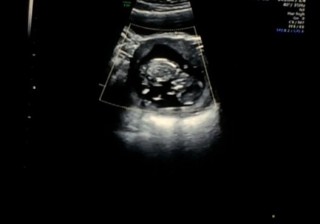

エコー写真

顔

• おなまえ小梅

• ねんれい35歳

• 妊娠週12w0d

妊娠9週から 絨毛膜下血腫で出血。自宅安静。 12週に 診察して血腫がなくなったと 診断していただいたときのエコーです! 赤ちゃん元気に 大きくなってました!